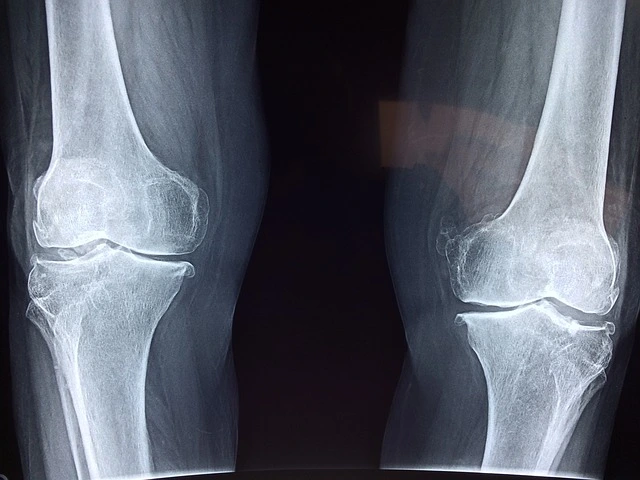

장맛비에 무릎이 아픈 것은 과학이다.

정확히 말하면 대기의 압력이 낮아져 관절 속에 있는 압력이 높아진다. 이러한 관절 속의 변화는 어르신들의 무릎과 허리 등등의 관절에 불편함을 준다.

위의 자료는 2019년도 퇴행성 관절염에 관련된 자료이며, 인터넷의 검색을 해보면 정확한 정보를 찾을 수 있을 것이다.